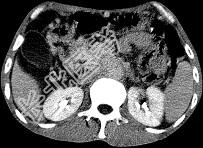

- 单项选择题女,50岁, 中上腹疼痛,消瘦乏力, 影像检查如下图,最佳的诊断是  (    )

- A、慢性胰腺炎

- B、急性胰腺炎

- C、胰腺癌并腹膜后淋巴结转移

- D、胰岛素瘤

- E、腹膜后淋巴瘤